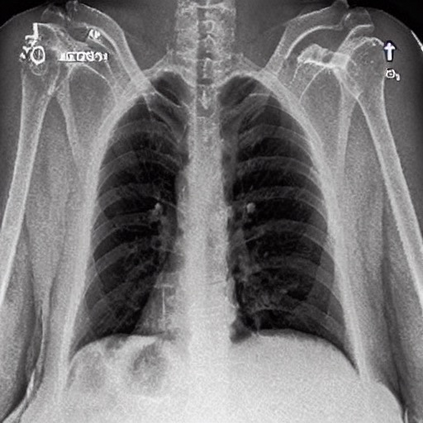

To address these issues, we propose a novel Adaptive patch-word Matching (AdaMatch) model to correlate chest X-ray (CXR) image regions with words in medical reports and apply it to CXR-report generation to provide explainability for the generation process. AdaMatch exploits the fine-grained relation between adaptive patches and words to provide explanations of specific image regions with corresponding words. To capture the abnormal regions of varying sizes and positions, we introduce the Adaptive Patch extraction (AdaPatch) module to acquire the adaptive patches for these regions adaptively. In order to provide explicit explainability for CXR-report generation task, we propose an AdaMatch-based bidirectional large language model for Cyclic CXR-report generation (AdaMatch-Cyclic). It employs the AdaMatch to obtain the keywords for CXR images and `keypatches' for medical reports as hints to guide CXR-report generation. Extensive experiments on two publicly available CXR datasets prove the effectiveness of our method and its superior performance to existing methods.